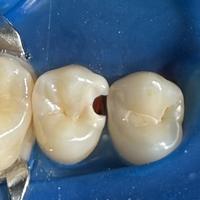

Коротко о бутылочном кариесе